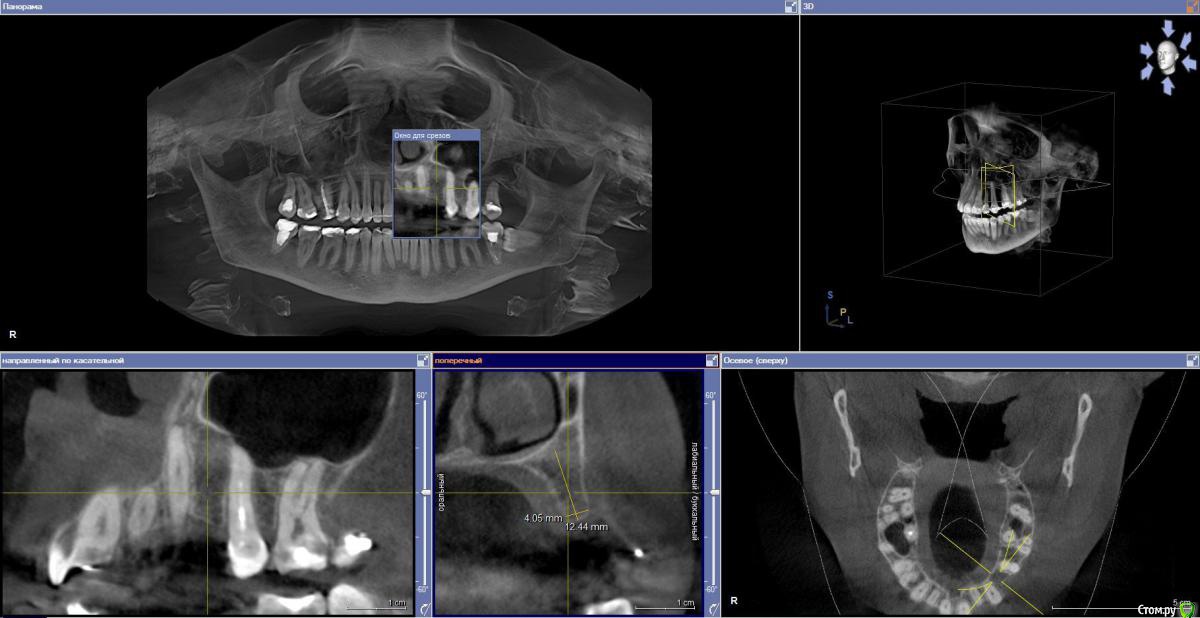

zarbazan Опубликовано 7 марта, 2019 Поделиться Опубликовано 7 марта, 2019 Планируется костная пластика и установка 1 имплантата.Как лучше сделать: сначала воссоздать объем кости, потом установка имплантата или одномоментно, с учётом что это первый опыт подобного вмешательства? Ссылка на комментарий

kramer Опубликовано 7 марта, 2019 Поделиться Опубликовано 7 марта, 2019 Я бы без костной пластики делал. Пилотное сверло, потом остеотомами конденсировал. Сразу винт + фдм или временная коронка Ссылка на комментарий

колесников Опубликовано 7 марта, 2019 Поделиться Опубликовано 7 марта, 2019 3.5х9. Фдм,ролл 1 Ссылка на комментарий